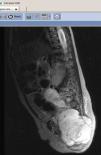

La paciente fue derivada al hospital de referencia donde se realizó una RM que mostró una gran masa pélvica de 11,7×6,1×7,3cm de diámetro (fig. 2), sólida, con áreas de necrosis y sangrado intralesional, así como un trombo en la vena cava inferior distal e ilíaca común izquierda. Se descubrieron nódulos metastásicos en la TC pulmonar. La determinación de marcadores tumorales mostró una elevación de la α-fetoproteína (14.400ng/ml, siendo los valores normales para la edad < 8) y una HCG normal, siendo diagnosticada de tumor del seno endodérmico con metástasis. Al ser diagnosticada de un proceso tumoral se retiró la acusación que pendía sobre la familia.